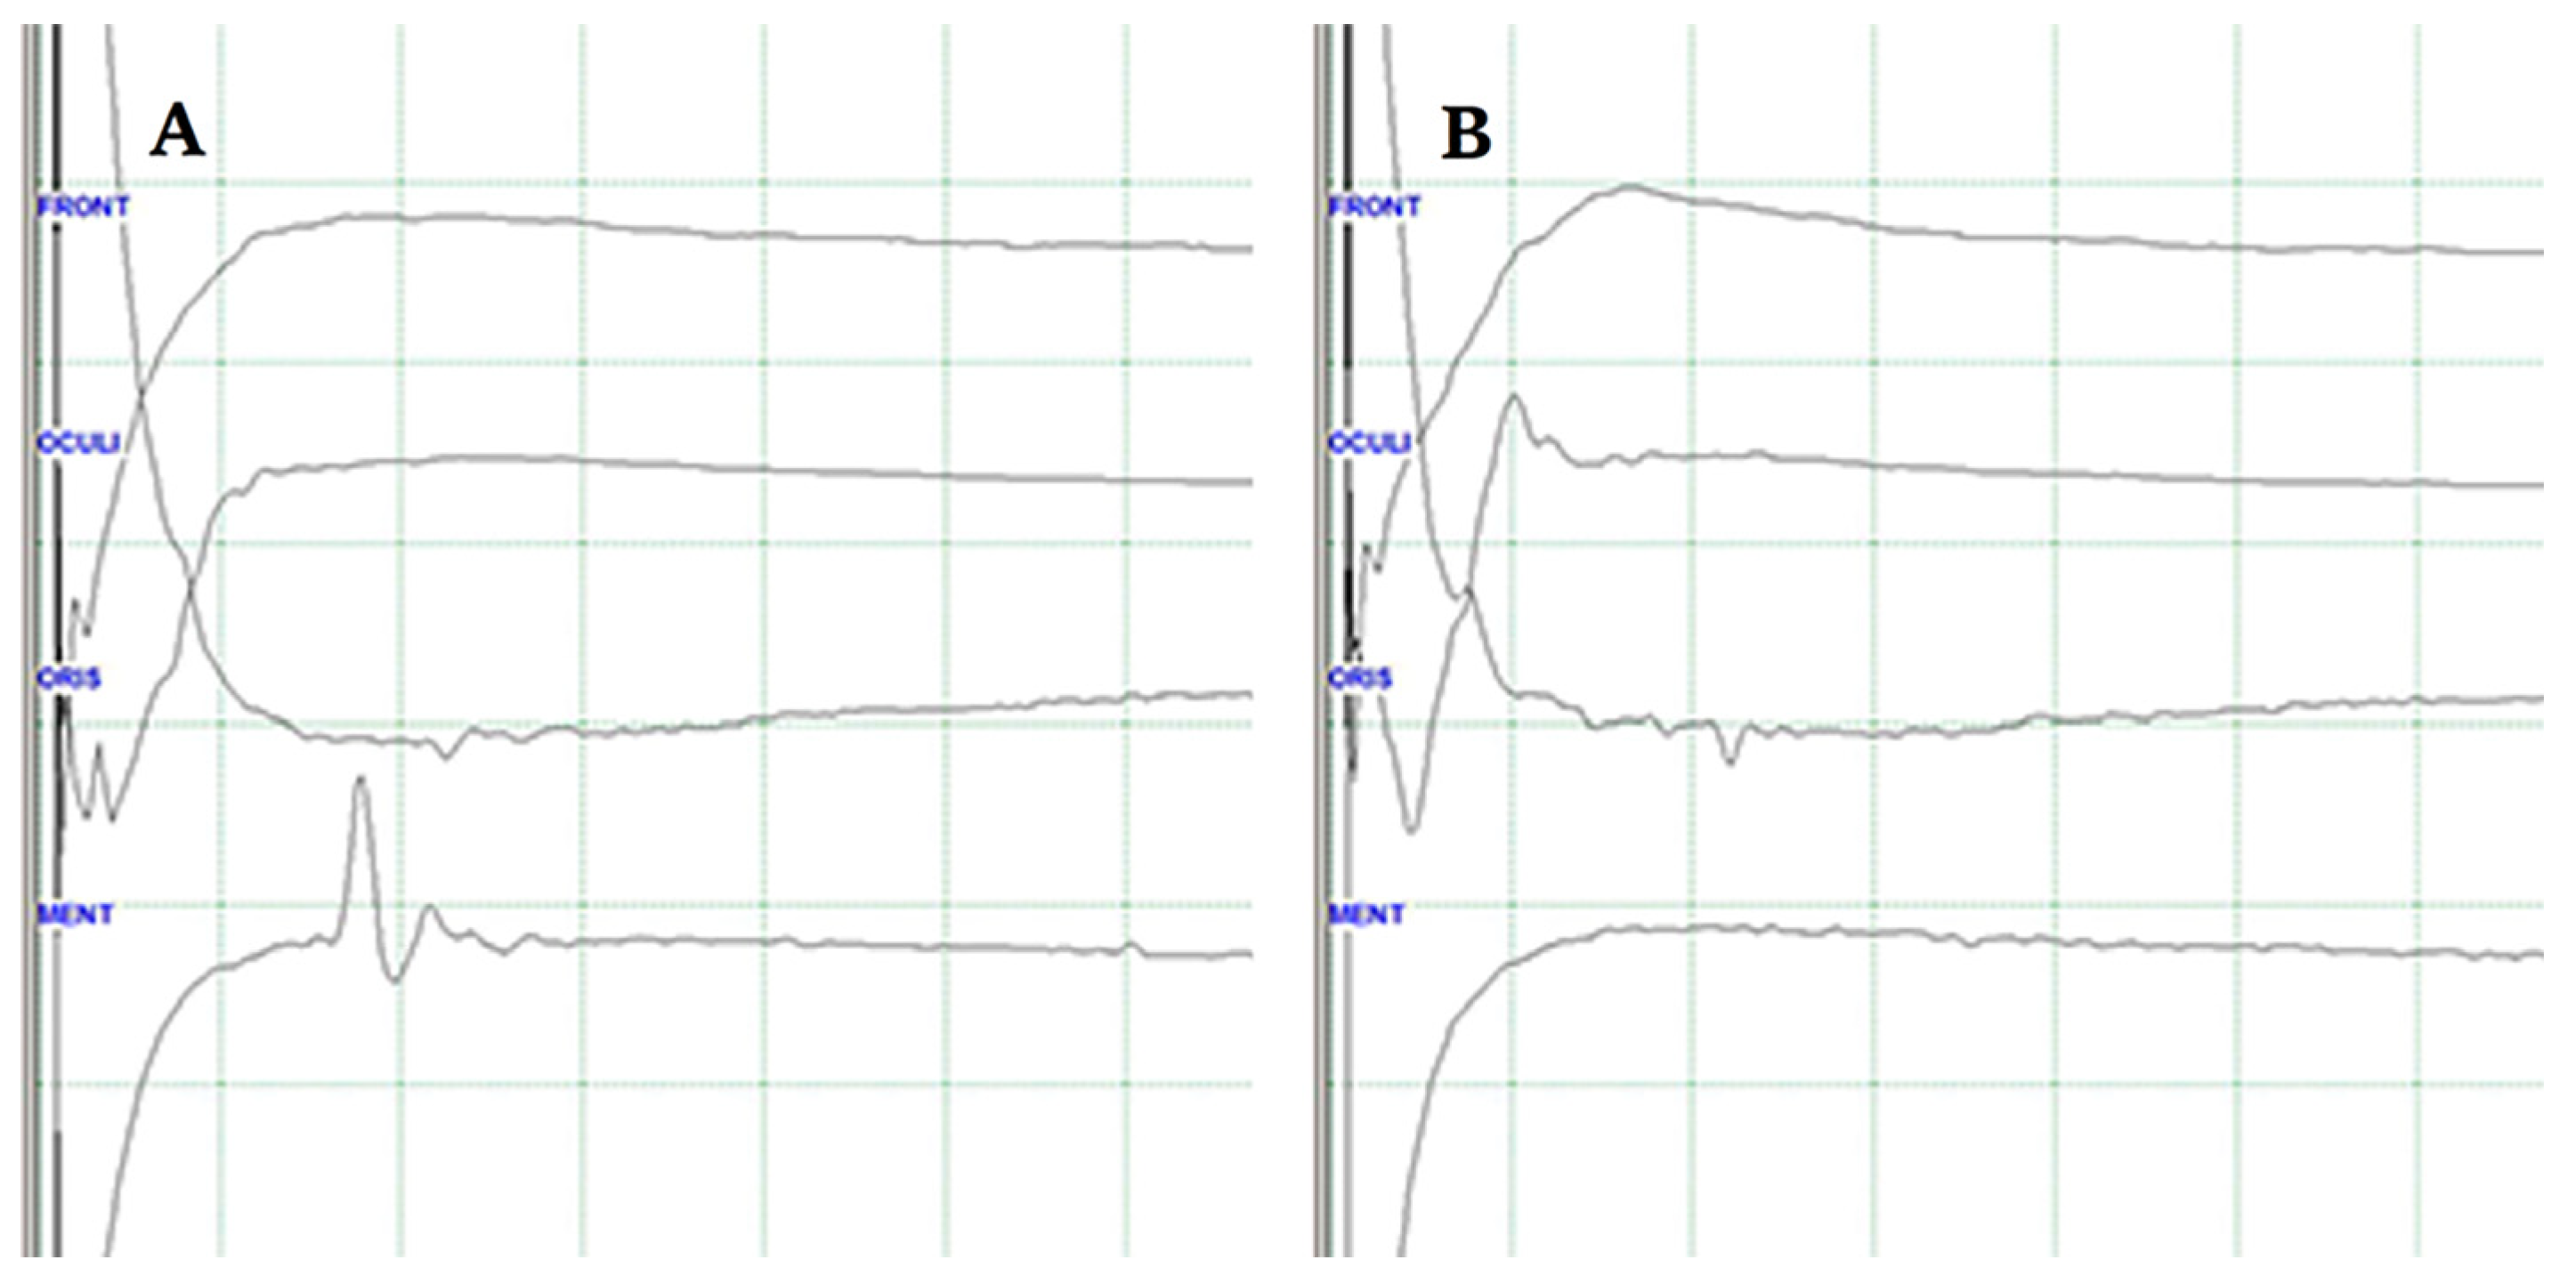

8. Confirmation of a Positive LSR

9. Confirmation of LSR Disappearance